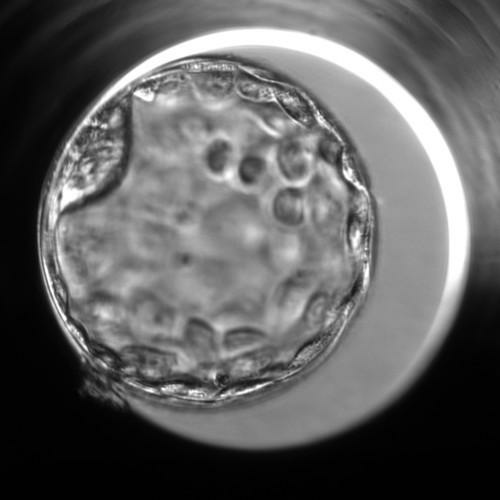

Automatic grading of human blastocysts from time-lapse imaging